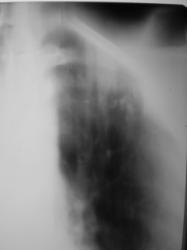

На фрагментах рентгенограмм (иллюстрации 3, 4), в прямой стандартной проекции слева под ключицей определяются полиморфные, различных размеров очаги.